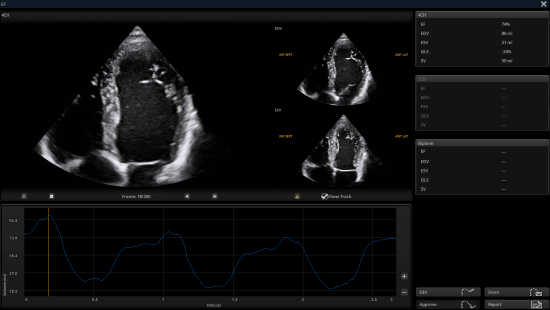

Auto EF facilitates cardiac systolic function assessment by automatically identifying and tracking the endocardium, and accurately calculating the LV EF within seconds.